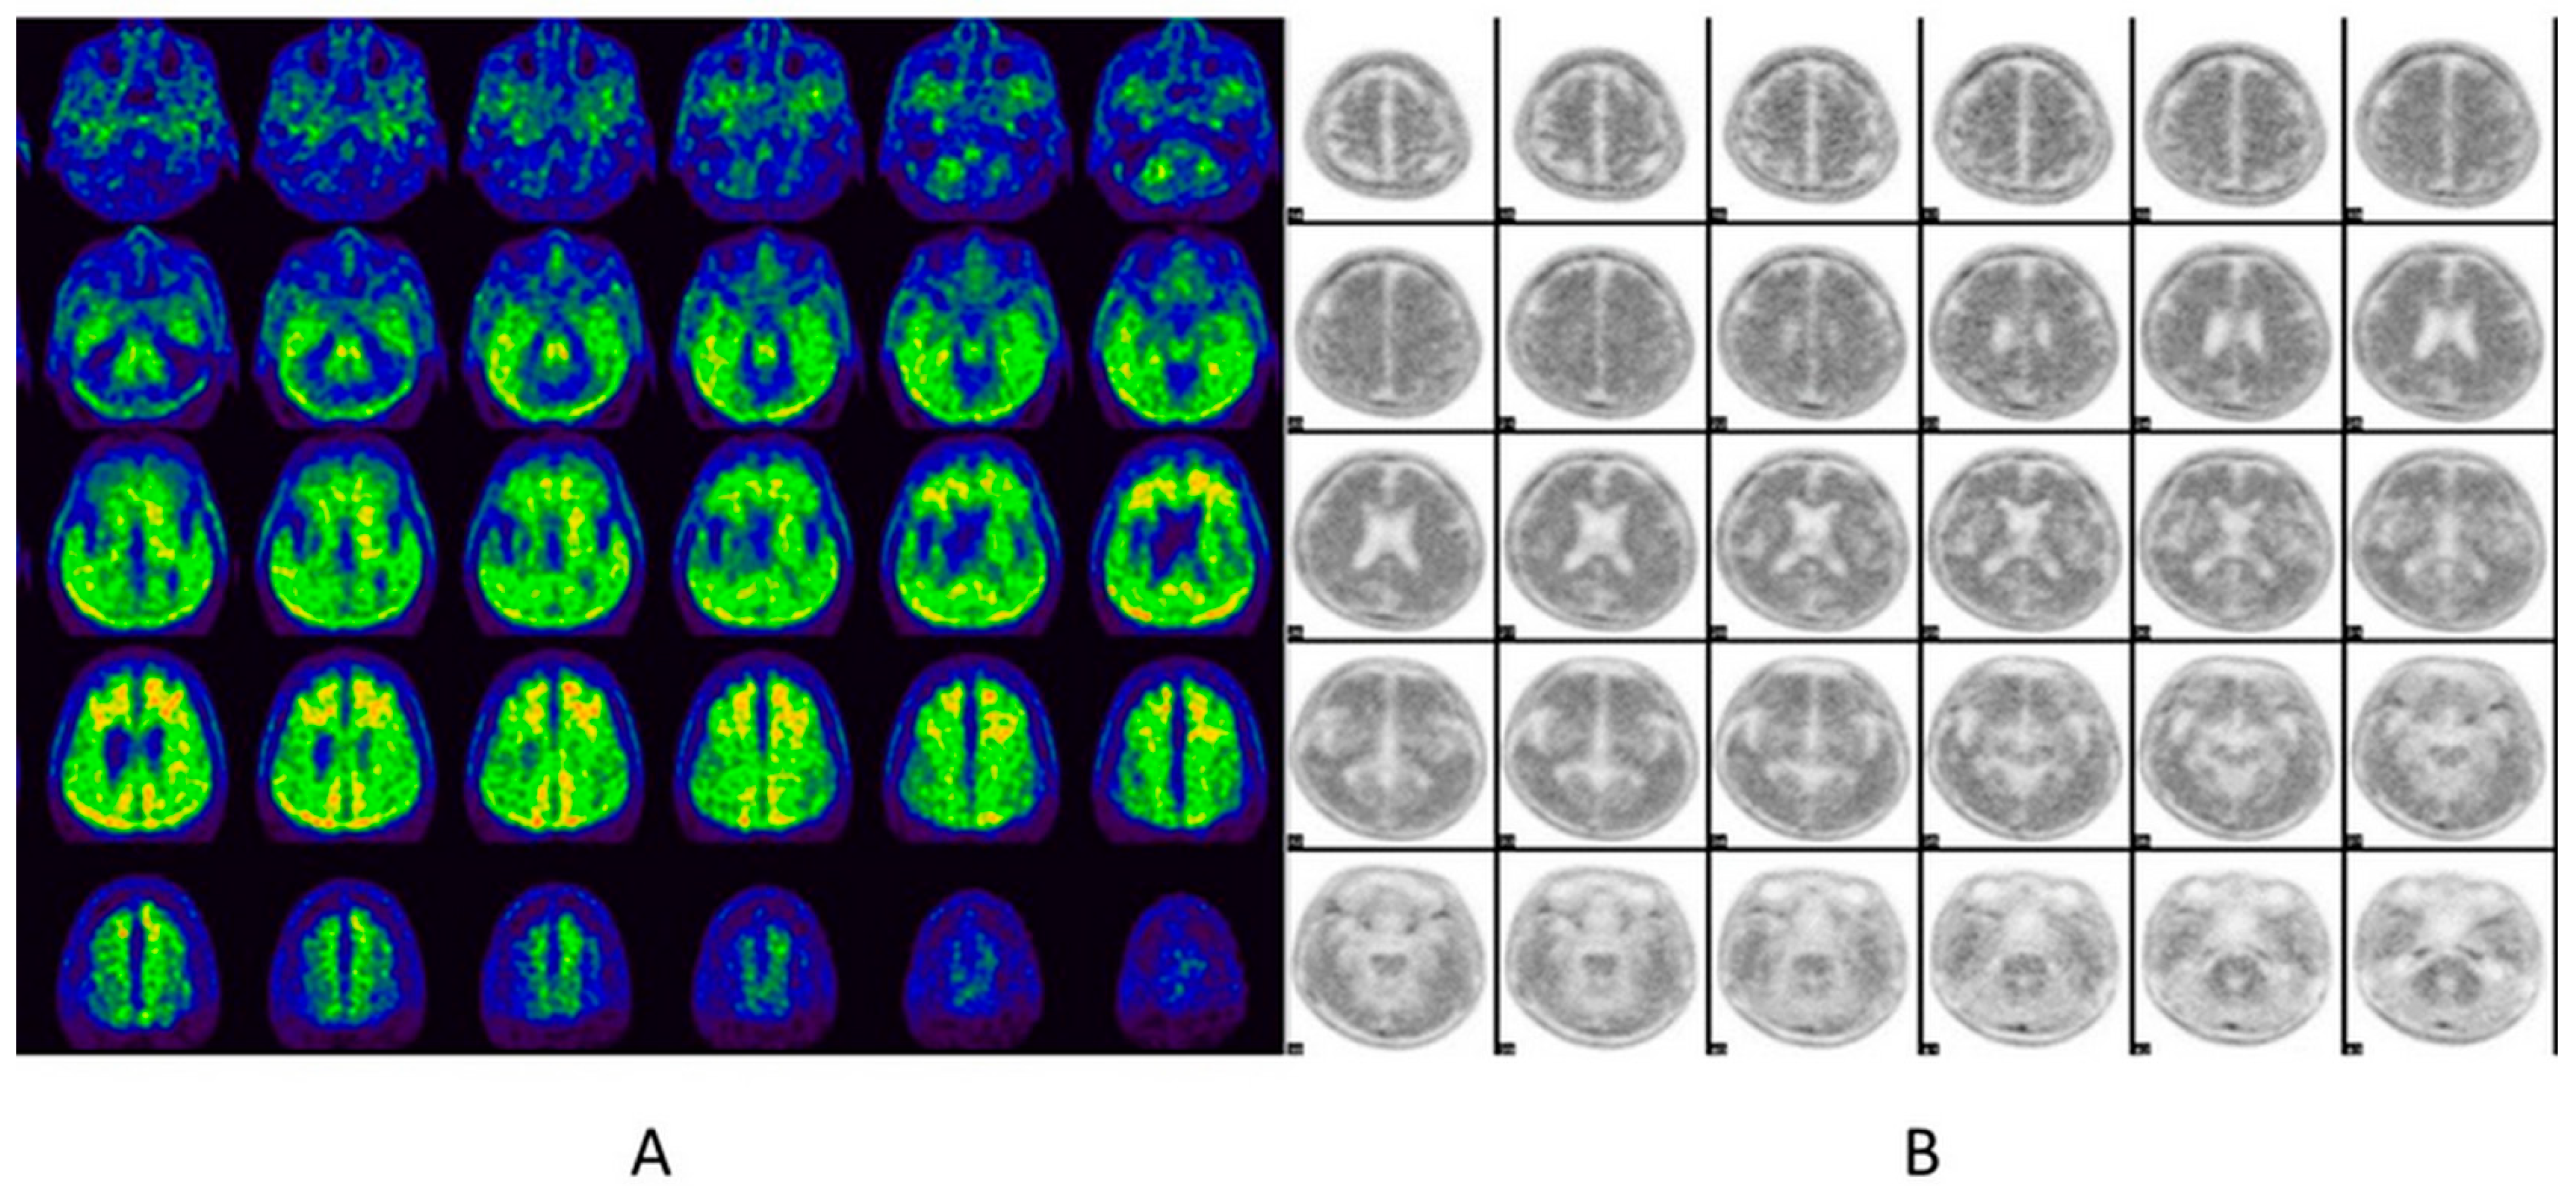

6.3. Tau PET

6.3.1. Imaging Data Display

6.3.2. Image Interpretation for Tau PET

Visual Analysis

Quantitative Analysis

6.3.3. Reporting Format

- -

- History: Indication, the patient’s clinical presentation, and correlative imaging.

- Techniques: Imaging is performed on an integrated 64-slice PET/CT scanner for the whole brain, with non contrast-enhanced CT for attenuation correction and localization in the transaxial, coronal, and sagittal planes. A 3D emission dynamic scan of the same area is acquired in a one-bed positionSemiquantitative calculations are performed using PMOD software with the automatic anatomical labeling (AAL)-merged atlas to generate automatic voxels of interest for different brain regions.

- Findings: Visual analysis: Describe abnormal tau deposition in the brain region.

- Interpretations/Impressions/Conclusions: Negative/positive studies should be mentioned when reporting the region of abnormal tau deposition.

| Tauopathy | Histopathology | Tau Isoform | |

|---|---|---|---|

| Electron Microscope | Light Microscope | ||

| Primary tauopathies | |||

| Progressive supranuclear palsy | SF (and TF) | Tufted astrocytes; globose tangles | 4R |

| Corticobasal degeneration | SF (and TF) | Astrocytic plaques | 4R |

| Argyrophilic grain disease | SF | Oligodendroglial coiled bodies; limbic argyrophilic grains | 4R |

| Pick’s disease | TF (and SF) | Pick’s bodies | 3R |

| Myotonic dystrophy | N/A | Neurofibrillary tangles | Short 0N3R |

| Secondary tauopathies | |||

| Alzheimer’s disease | PHF (and SF) | Neurofibrillary tangles | 3R and 4R |

| Down syndrome | PHF (and SF) | Neurofibrillary tangles | 3R and 4R |

| Chronic traumatic encephalopathy | PHF (and SF) | Neurofibrillary tangles | 3R and 4R |

| Niemann-Pick disease type C | PHF (and SF) | Neurofibrillary tangles | 3R and 4R |